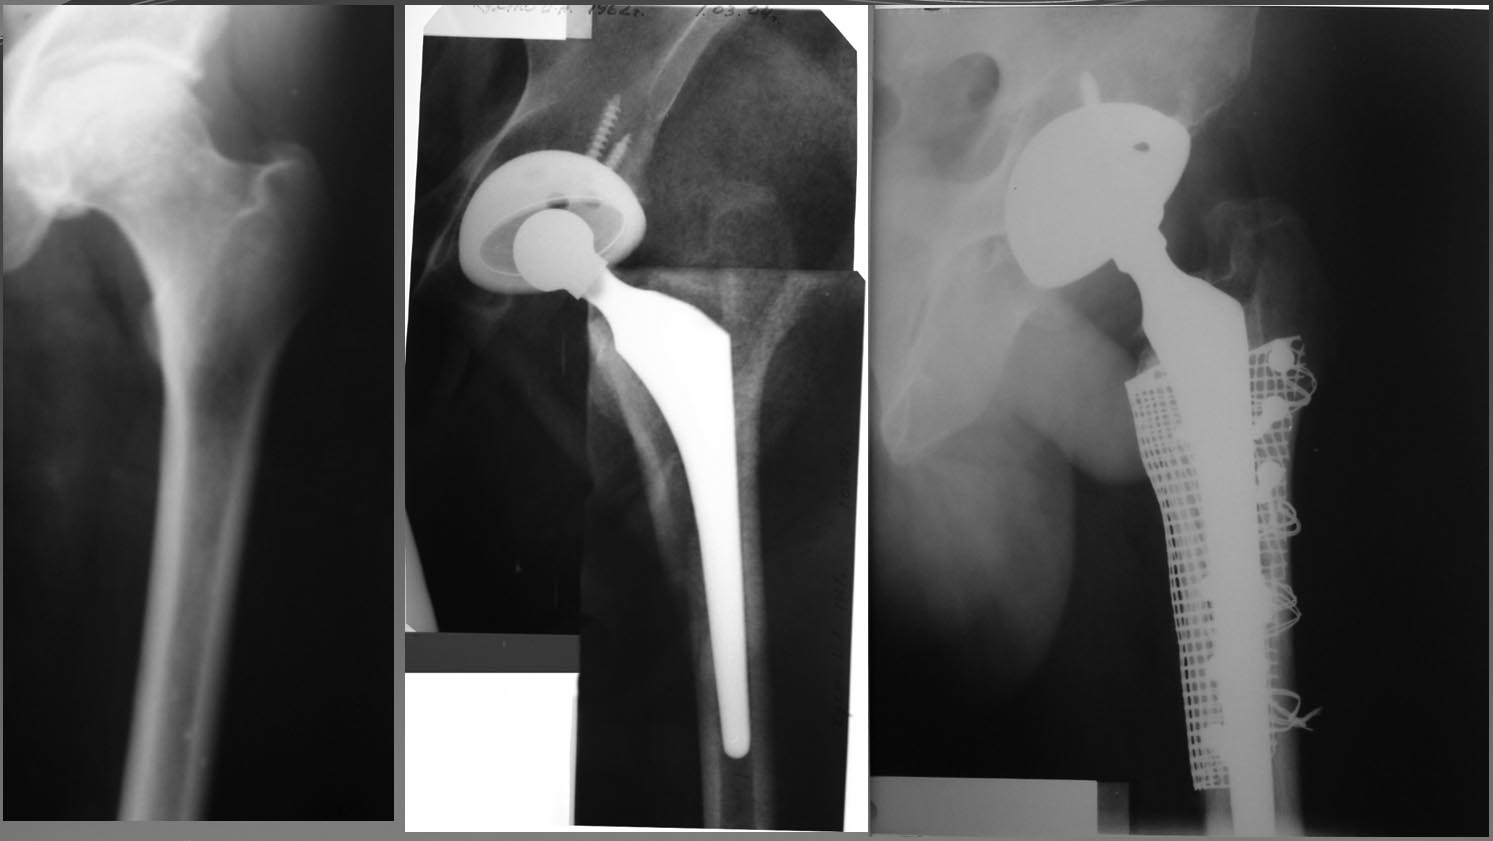

Для коллекции. Этот же пациент.

> Вот случай лечения перипротезного перелома Страйкеровской сеткой. 7 лет -

> полет нормальный.